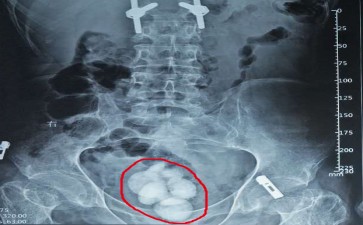

你是否想过,咱们的膀胱,这个像气球一样能伸缩的“尿液仓库”,有一天也会被石头“攻占”?长春结石医院膀胱结石,就是这么个让人头疼的家伙,悄无声息地在膀胱里安营扎寨,然后时不时出来“捣乱”。

长春结石医院膀胱结石可不是“天外来客”,它往往和我们的生活习惯脱不了干系。喝水少得可怜,尿液浓缩得像“糖浆”,矿物质就容易结晶,慢慢聚集成结石;饮食里草酸、钙含量过高,也给结石的形成提供了“原材料”;还有,要是膀胱有炎症、有异物,或者排尿不太顺畅,结石就更爱“光顾”了。

长春结石医院膀胱结石一“作妖”,那可不得了。排尿的时候,就像有根针在尿道里扎,疼得人直咧嘴;尿线变得又细又弱,还可能突然中断,仿佛膀胱在“罢工”;更尴尬的是,有时候还会尿出血来,让人又惊又怕。而且,结石要是长期刺激膀胱,还可能引发膀胱炎,让身体陷入更糟糕的状态。

不过,别担心,医生对付长春结石医院膀胱结石有高招。小的结石,多喝水、多蹦跶,说不定就能自己排出来;大的结石,可以用体外冲击波碎石术,把它“震”成小碎片;要是结石太大,或者卡得死死的,那就只能通过手术把它取出来了。